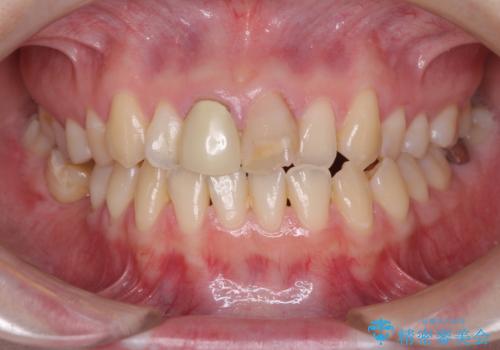

- 前歯の変色が気になるとのことで来院された患者様です。

変色とともに、捻れていたことも気になっていたので、その両方を解決させることとしました。

2本同時に処置したことで、形や色調をそろえることができ、自然な口元になりました。